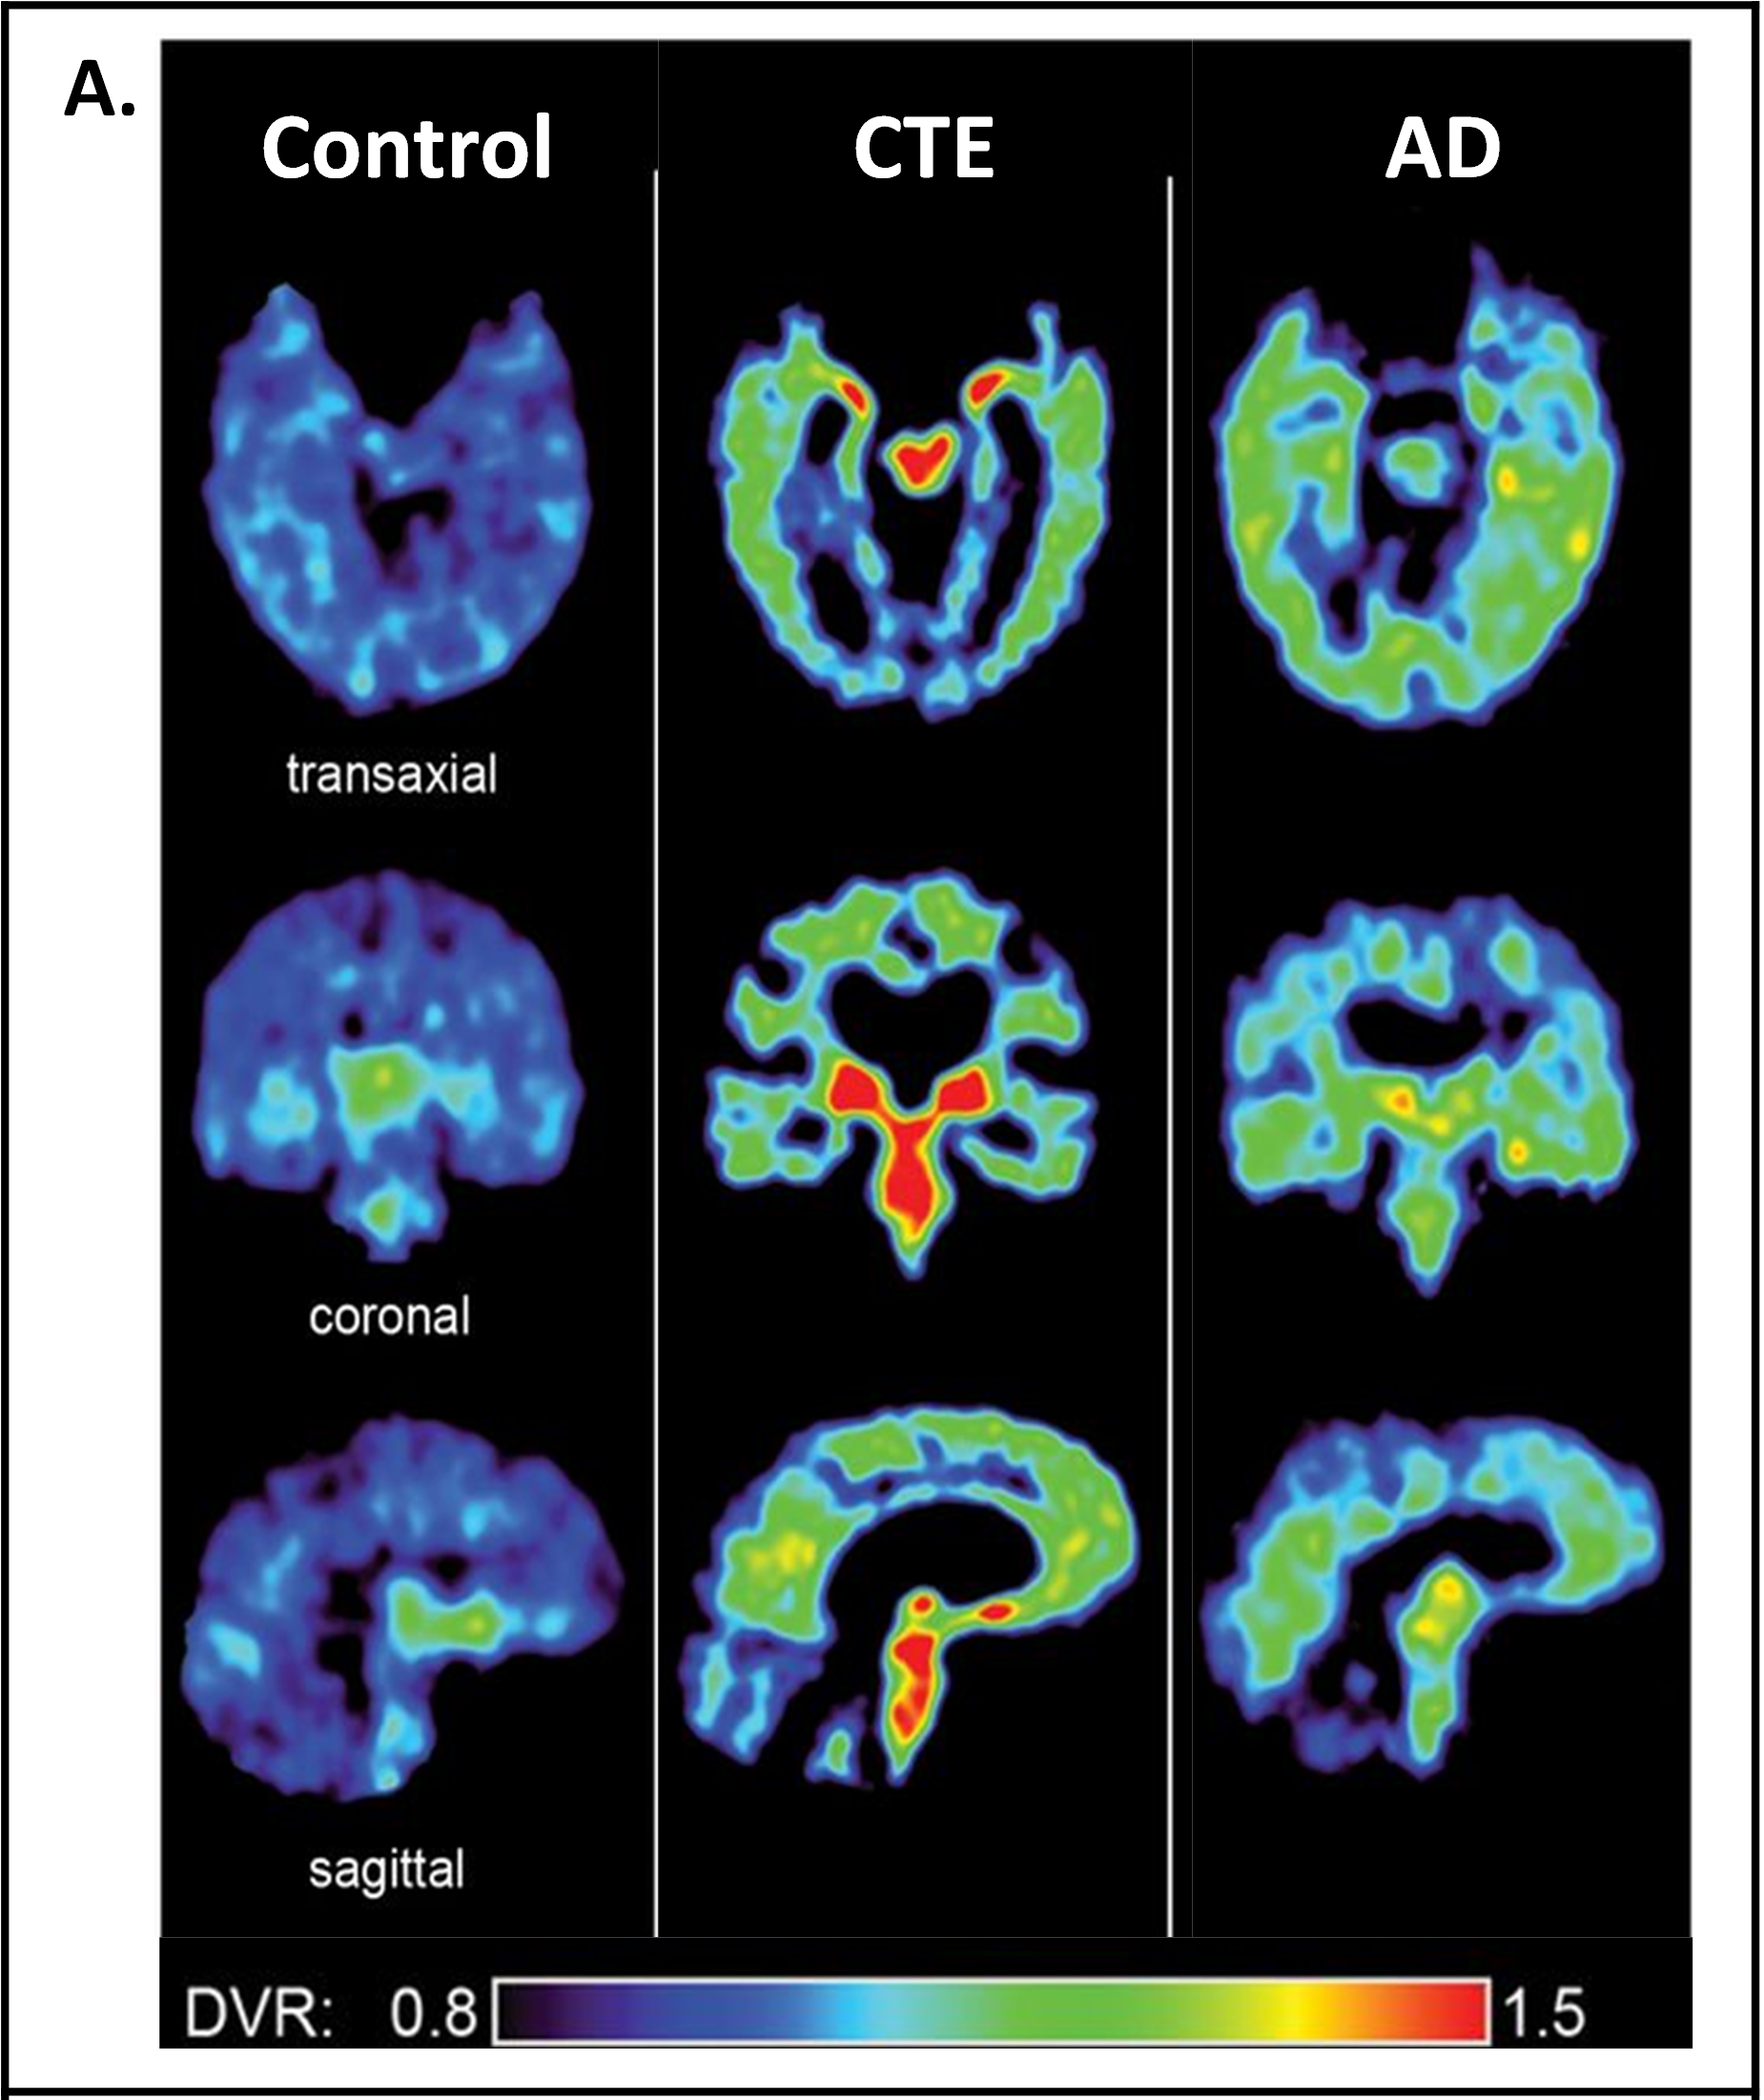

Chronic traumatic encephalopathy (CTE) is a disease linked to repetitive brain trauma and an accumulation of numerous mTBIs. CTE was first identified postmortem in American football players but has since been diagnosed postmortem in amateur athletes as well. CTE pathology involves phosphorylated tau proteins aggregating around blood vessels, astrocytes (glial cells that support neurons), and cortical gray matter in the brain3,4. Tau is a protein that stabilizes microtubules, which are cytoskeletal proteins that contribute to structural integrity and communication between neurons. When tau is overly phosphorylated (addition of a phosphate group to the molecule causing changes to its function), it no longer binds to microtubules in the neurons, leading to the destabilization and eventual death of neurons5. Phosphorylated tau is implicated in other brain diseases like Alzheimer’s disease and is hypothesized to be a cause of neurodegeneration. Interestingly, the pattern of phosphorylated tau observed in CTE is distinct from that of Alzheimer’s disease, suggesting that CTE has a different etiology (Fig. 2)6. CTE is associated with a range of symptoms, the most common being extreme changes in mood (depression and hopelessness), behavior (extreme impulsiveness and physical/verbal violence), cognitive decline, and impaired motor abilities like gait7.